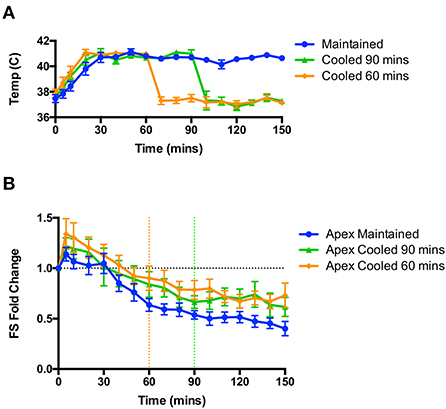

Cooling animals back to euthermia after the initial induction phase does not reverse or attenuate the apical dysfunction caused by high dose isoproterenol

As hyperthermia was essential to the induction of apical dysfunction, we hypothesized that restoration of a euthermic body temperature would either attenuate or reverse the dysfunction. In a separate set of studies shown in Figure 4, rats were randomized prior to study either to be cooled at 60 or 90 min post-isoproterenol, or be maintained at 41°C; all animals were studied to 150 min post-isoproterenol regardless of group. Through the application of cooling packs we were able to rapidly reduce the body temperature back into the euthermic range (Figure 4A). We found no significant change in apical hypocontractility in either cooled group compared to the maintained group; apical hypocontractility was sustained in all three groups (Figure 4B).

Figure 4. Rapid cooling of animals after the induction of apical dysfunction did not reverse or attenuate the hypocontractility. (A) Rapid changes in body temperature could be achieved through the application of cooling. (B) No effect of cooling was observed on apical dysfunction on rats cooled at 60 min (from orange dotted line) or 90 min (from green dotted line); n = 6 animals per group. Repeated measures ANOVA.